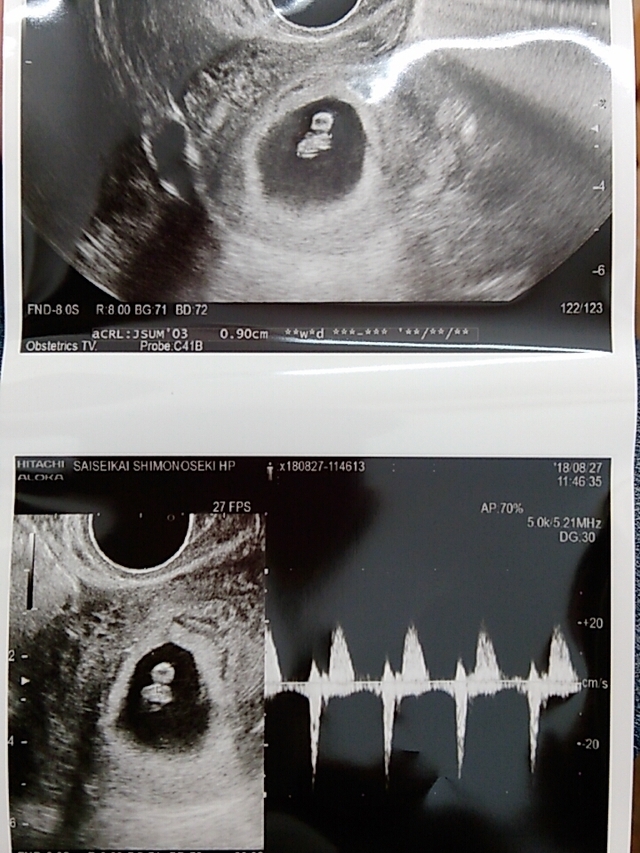

8週5日(8w5d・女の子)|ayakaa04 さん(29歳)

エコー写真撮影時のエピソード:やっとこ心拍を確認させてくれた我が子。クリオネのようにプカプカ浮きながらも力強い心拍を私に聞かせてくれた。まだまだ実感のわかない主人ではありましたが、このときのエコー動画を見せると感動し、お腹をさすってくれた。二人で子どもを育てていくとやっと足並みが揃った日であった。トクトクと鼓動を奏でる我が子を確認できたことが、私達の特別な日となった。